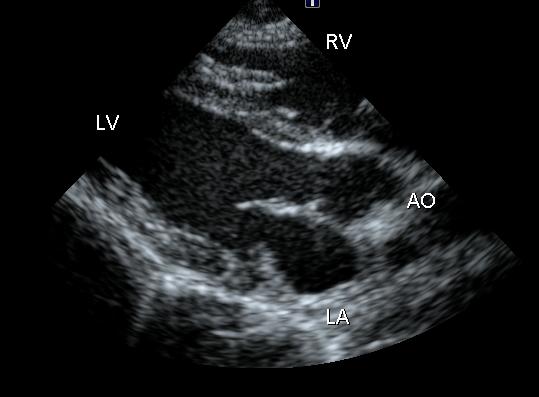

●左室流出路断面

@左心房径、大動脈径、心室中隔壁、左室後壁厚、右室壁厚、左心室腔内径を観察

A異常を感じれば、Mモードおよびカラードプラで詳細検査

●大動脈断面

@大動脈、大動脈弁、左房、左心耳を観察